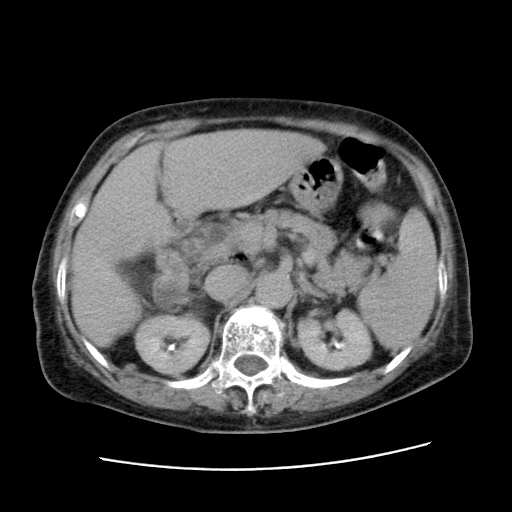

女,77.无不适

肝脏变异、异位胆囊,肝右叶肝内胆管结石并肝内胆管扩张。

肝右叶肝内胆管结石并肝内胆管扩张。

肝右叶肝内胆管结石并肝内胆管扩张

胆总管扩张

肝旁多发胆囊状液体影考虑肠腔积液基中部分囊状景不多外胆囊

肠子那块乱乱的没整明白

肝右叶肝内胆管结石并肝内胆管扩张。胆总管下段梗阻,考虑壶腹部占位。

右侧肝内胆管局限性扩张,其内密度不均匀,扩张的胆管壁增厚,考虑肝内胆管炎合并结石可能性大

肝右叶肝内胆管结石并肝内胆管扩张。胆总管下段梗阻,考虑壶腹部占位。支持